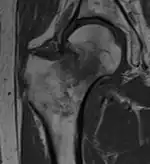

T1-weighted turbo spin echo MRI confirms a fracture, as the surrounding bone marrow has low signal from edema.